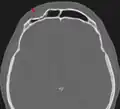

Beim Menschen finden sich gelegentlich Osteome in der Stirnhöhle.

Osteom der Stirnhöhle in der Computertomographie -